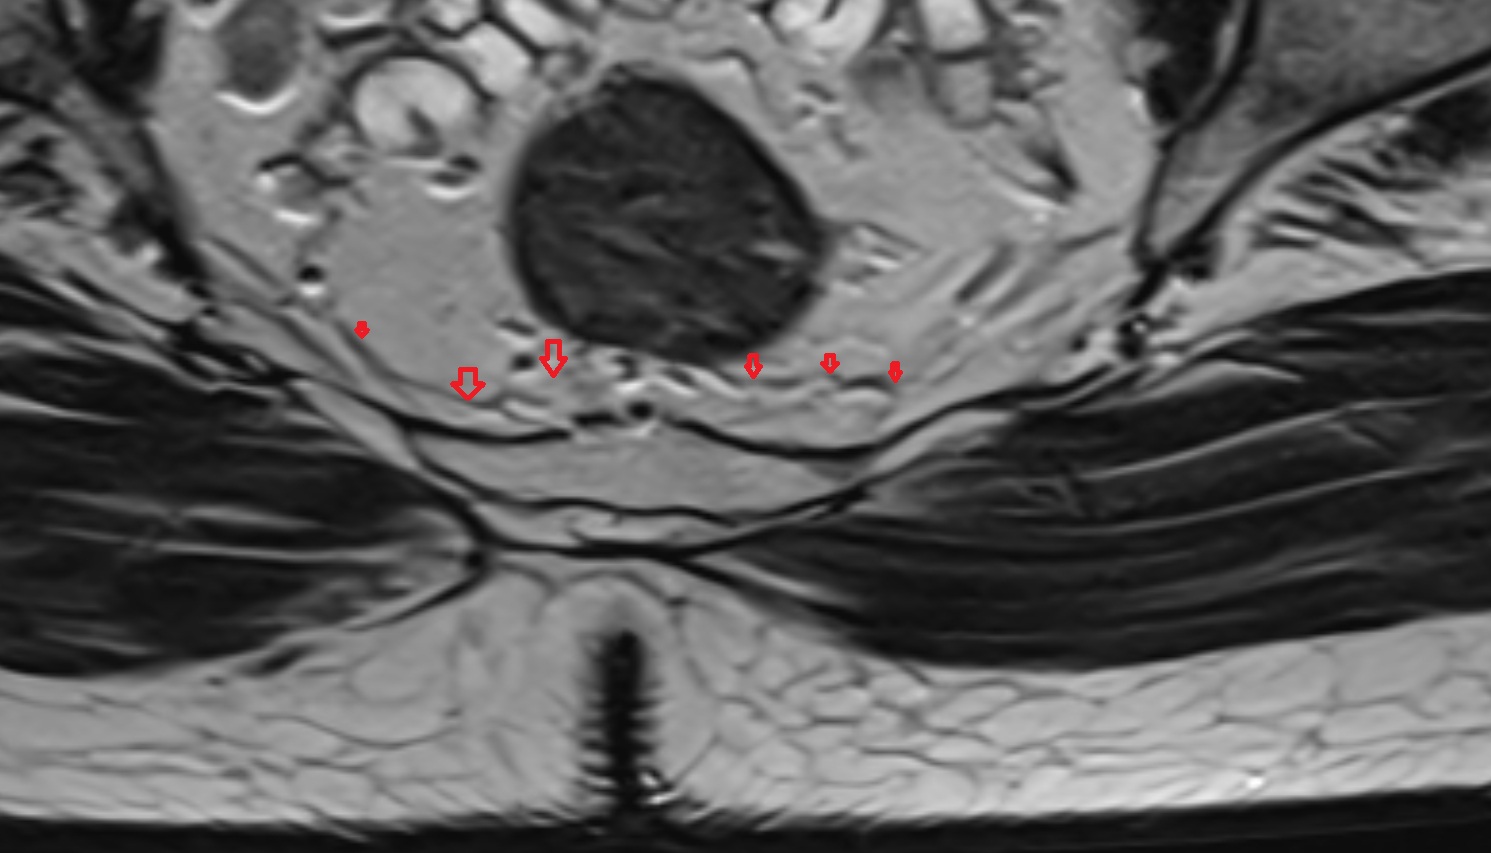

- Mesorectal fascia

- Mesorectum

- Peripheral zone of prostate

- Anterior Fibromuscular Stroma of prostate

- Central zone of prostate

- Transitional zone of prostate